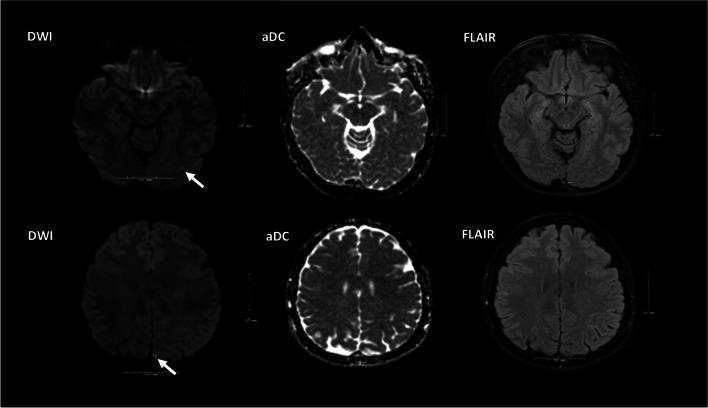

Randomized controlled trials (RCT) on the best medical therapy in the treatment of cervical artery dissection (CeAD) have demonstrated low rates of ischemia with both antiplatelet and vitamin K antagonism. RCT evidence supports the use of anticoagulation with vitamin K antagonism in "high-risk" patients with antiphospholipid antibody syndrome (APLAS), and there is new evidence supporting the utilization of direct oral anticoagulation in malignancy-associated thrombosis. Migraine with aura has been more conclusively linked not only with increased risk of ischemic and hemorrhagic stroke, but also with cardiovascular mortality. Recent literature has surprisingly not provided support the utilization of L-arginine in the treatment of patients with mitochondrial encephalopathy, lactic acidosis, and stroke-like episodes (MELAS); however, there is evidence at this time that support use of enzyme replacement in patients with Fabry disease. Additional triggers for reversible cerebral vasoconstriction syndrome (RCVS) have been identified, such as capsaicin. Imaging of cerebral blood vessel walls utilizing contrast-enhanced MRA is an emerging modality that may ultimately prove to be very useful in the evaluation of patients with uncommon causes of stroke. A plethora of associations between cerebrovascular disease and COVID-19 have been described. Where pertinent, authors provide additional tips and guidance. Less commonly encountered conditions with updates in diagnosis, and management along with clinical tips are reviewed.

关于颈内动脉夹层(CeAD)最佳药物治疗的随机对照试验(RCT)表明,抗血小板和维生素 K 拮抗剂的缺血发生率均较低。RCT 证据支持在抗磷脂抗体综合征(APLAS)的“高危”患者中使用维生素 K 拮抗剂抗凝,并且有新的证据支持在恶性肿瘤相关血栓形成中使用直接口服抗凝剂。有先兆偏头痛不仅与缺血性和出血性卒中风险增加有关,而且与心血管死亡率有关,这一点已得到更明确的证实。最近的文献并没有提供支持使用精氨酸治疗线粒体脑肌病、乳酸酸中毒和卒中样发作(MELAS)患者的证据;然而,目前有证据支持在 Fabry 病患者中使用酶替代治疗。已经确定了可逆性脑血管收缩综合征(RCVS)的其他触发因素,如辣椒素。利用对比增强 MRA 对脑血管壁进行成像,是一种新兴的模式,最终可能在评估不常见卒中病因的患者中非常有用。描述了大量与 COVID-19 相关的脑血管疾病的关联。作者提供了额外的提示和指导,针对与这些关联相关的内容。我们还回顾了一些诊断和管理方面有更新的、不太常见的疾病,并提供了临床提示。